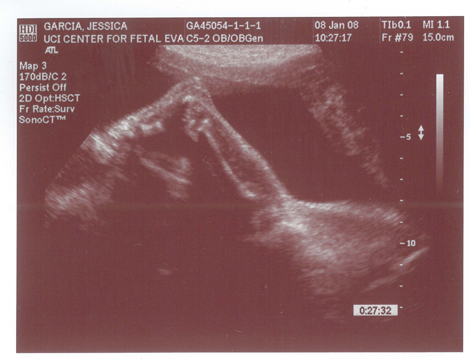

Babies First Pictures!!! ITS A BOY!

Yes we got a new dsmer coming into the world soon. We got our ultrasound today and its gonna be a boy. And shes a lot further along then we had originally thought. Shes due on April 15th which puts her at almost 6.5 months, (and really not showing it.) He weighs currently ~2lbs. He even opened his mouth while on camera which was really cool.

Here are the pics.

Pic 1: The babies head profile

Pic 2: Mouth is open!

Pic 3: NWS Baby Penis! lol

Pic 4: Long little legs!

Pic 5: Big Feet just like his mama.